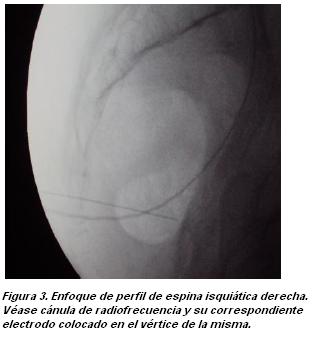

Se realizó el procedimiento en posición decúbito ventral. Se colocó via venosa periférica. Monitorización con oxímetro de pulso y electrocardiograma. Asepsia con clorhexidina alcohólica en ambas regiones glúteas. Se localiza por radioscopia la espina isquiática izquierda, colocando arco en C inicialmente en posición antero-posterior y luego oblicua aproximadamente 15 grados homolateral. Se realiza anestesia local en la piel con lidocaína al 0.5%, 4 ml. Se introduce una aguja de quincke número 22, de 90 mm, en visión túnel hasta contactar con la espina isquiática correspondiente (figura 1). Se realizó 5 cc bupivacaína al 0.5 % a ese nivel y luego se repite el procedimiento del lado derecho.

A la semana el paciente presentó alivio de más de un 50% de su dolor inicial, con mejoría funcional importante, respuesta de aproximadamente 4 a 6 semanas de duración. Dos semanas después se repite procedimiento con respuesta evolutiva similar. Se plantea la realización de una radiofrecuencia pulsada de ambos nervios pudendos. En condiciones previas similares a las descritas para el bloqueo con anestésicos locales, se punciona con cánula de radiofrecuencia número 22 de 10 de cm con 1 cm de punta activa, dirigiendo con visión túnel hacia el vértice de la espina isquiática derecha (figura 2) hasta hacer contacto óseo. Luego se realiza prueba sensitiva con siendo positiva a 0.5 milivoltios. El paciente relato dolor a nivel perineal, en la misma topografía que el dolor que motivo su consulta. Se realizó 2 cc de lidocaína al 0.5%. Se comprobó nuevamente posición de la aguja en espina isquiática en con arco en C en posición oblicua y perfil (figuras 2 y 3). A continuación se realizaron dos sesiones de radiofrecuencia pulsada de 120 segundos cada una a 45 a 50 voltios, 42 grados de temperatura. Luego se inyectaron 5 cc de una solución de lidocaína al 0.5 % mas 25 mg de triamcinolona. Se procedió del mismo modo del lado contralateral. También en este caso se obtuvo respuesta sensitiva a la estimulación a 0.5 voltios, despertando dolor de las mismas características a nivel perineal. El procedimiento se desarrollo sin incidentes. El paciente presentó los días siguientes un incremento moderado de su dolor, retornando luego éste a sus condiciones basales. Este incremento del dolor luego del procedimiento se tomó como limitante para repetir un nuevo intento de radiofrecuencia.